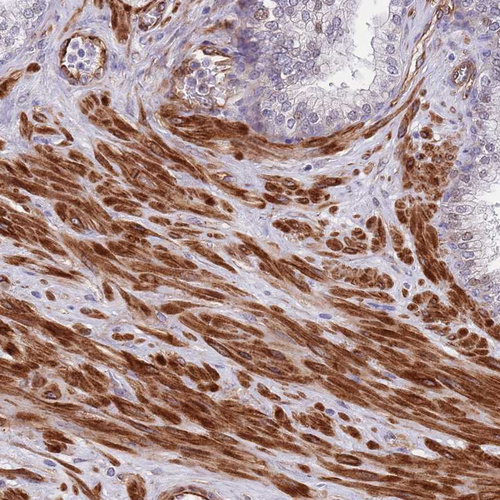

Immunohistochemical staining of human small intestine shows strong cytoplasmic positivity in glandular cells.